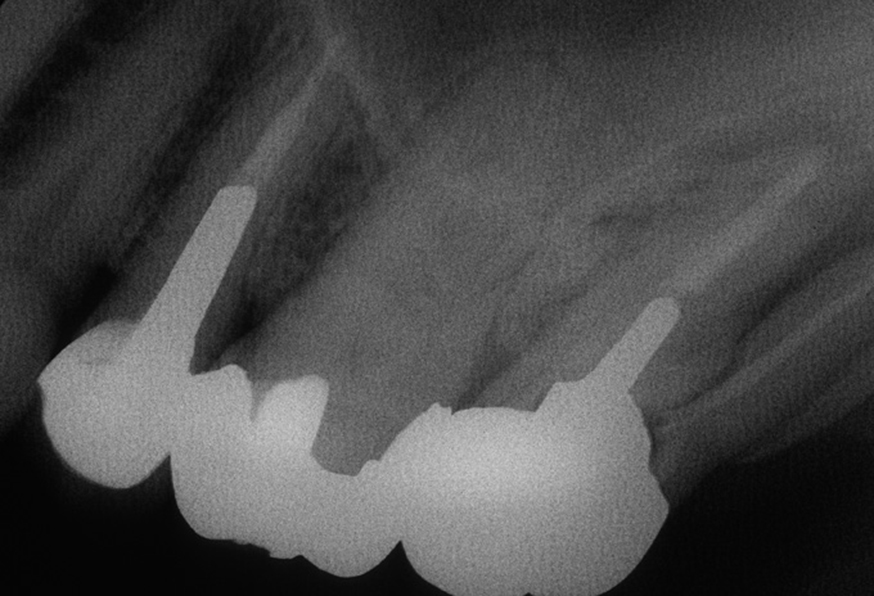

図2 術前レントゲン写真

この角度からだと破折はよく分かりませんので、角度を変えてレントゲンを追加します

図3 術前レントゲン写真 近心投影

この角度のレントゲン写真だと分かりやすいです